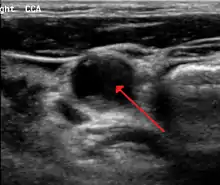

70 percent stenosis of the right internal carotid artery as seen by ultrasound. Arrow marks the lumen of the artery.

Carotid artery stenosis is usually diagnosed by color flow duplex ultrasound scan of the carotid arteries in the neck. This involves no radiation, no needles and no contrast agents that may cause allergic reactions. This test has good sensitivity and specificity.[11]